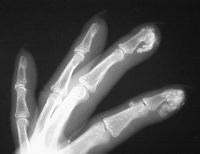

The right index and middle fingertips are large, hard and tender.

Xrays show extensive soft tissue calcifications of the distal pulp of these fingers.